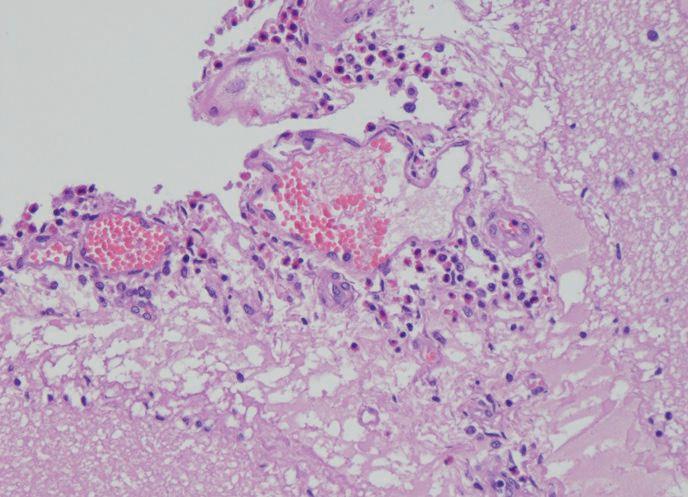

Results The pigs were diagnosed with eosinophilic meningoencephalitis, associated with salt poisoning or obstructed water intake. The meningoencephalitis was characterized by an increased presence of eosinophilic granulocytes in the brain (Fig. 1), concurrent with neuronal

Figure 1: Cerebrum. A blood vessel is surrounded by eosinophilic granulocytes, characterized by granular pink cytoplasm. Hematoxylin and eosin (H&E) stain.